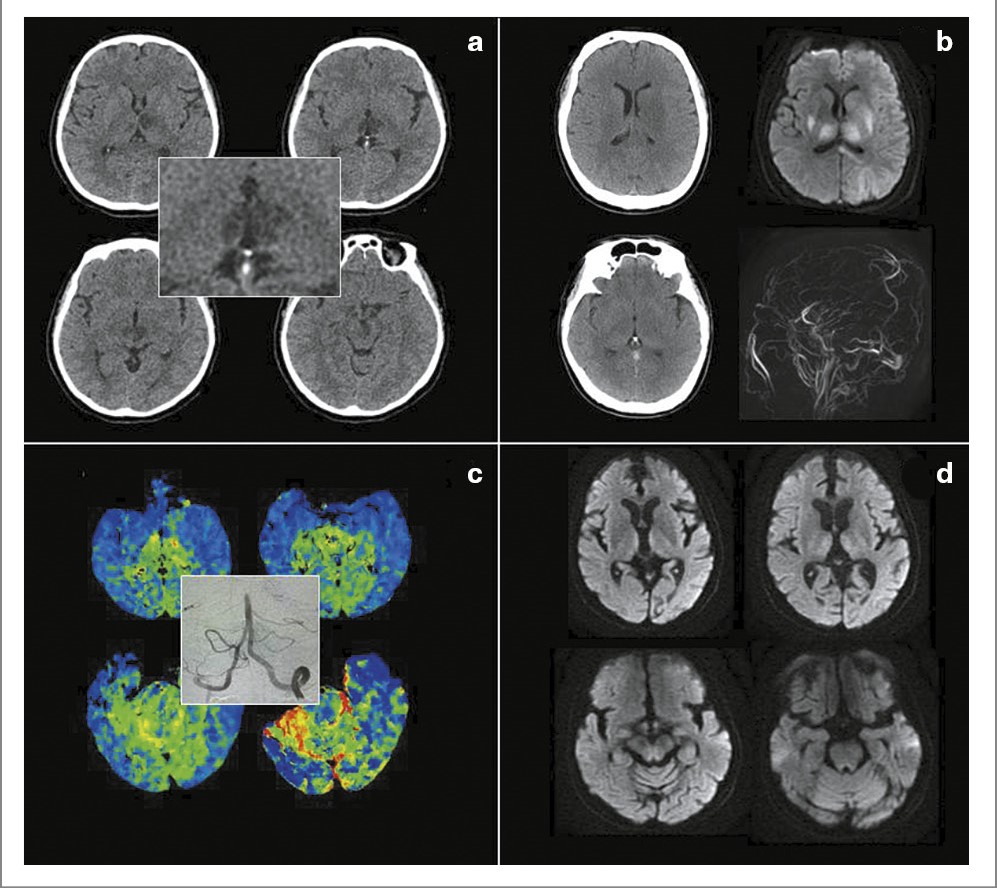

Рис. 2. Клинические случаи внутривенного тромболизиса при инсульте в бассейне АП.

Случай 1. Мужчина 57 лет без сердечно-сосудистых заболеваний в анамнезе. После длительного переезда внезапно возникло двоение перед глазами. Позвонил родственнику, который позже застал пациента сонливым и вызвал бригаду скорой медицинской помощи. Поступил в стационар через 1,5 ч от развития симптомов сомноленции (a), продуктивный контакт не был возможен из-за снижения бодрствования и выраженных когнитивных нарушений. При проведении КТ и КТ-ангиографии патологии не выявили. По данным КТ-перфузии отмечена зона гипоперфузии в медиальных отделах обоих таламусов (b). Провели внутривенный тромболизис препаратом Фортелизин® с полным клиническим восстановлением. МРТ через сутки продемонстрировала зону ограничения диффузии в медиальных отделах обоих таламусов (c). Очаг в среднем мозге не сформировался (d). Пациент отказался от дальнейшего обследования и был выписан с диагнозом «ишемический инсульт неизвестной этиологии в бассейне АП». При этом анамнез заболевания позволяет думать о парадоксальной эмболии.

Случай 2. Женщина 73 лет с длительным анамнезом гипертонической болезни. В 8:00 внезапно появилось двоение перед глазами, вызвана бригада скорой медицинской помощи. Во время транспортировки развилась слабость во всех конечностях, появились нечеткость речи, оглушение. Поступила в стационар через 2,5 ч от развития симптомов. В неврологическом статусе наблюдался вертикальный парез взора (e), дизартрия и тетрапарез. При проведении КТ визуализирована лакуна в медиальных отделах левого таламуса (f). КТ-ангиография не выявила патологии. По данным КТ-перфузии отмечена зона гипоперфузии в медиальных отделах правого таламуса (f; в рамочке). Провели внутривенный тромболизис препаратом Фортелизин® с регрессом неврологического дефицита в течение часа (g; показано восстановление взора вверх). МРТ через сутки продемонстрировала зону ограничения диффузии в медиальных отделах левого таламуса (h). В других зонах, связанных с клинической картиной, инфарктов не сформировалось. Установлен лакунарный инсульт в бассейне АП, однако второе событие в одном и том же бассейне повышает вероятность атероматоза перфоранта.

Рис. 3. Дифференциальная диагностика инсульта в бассейне АП: a – пример КТ-визуализации при тяжелом инсульте в бассейне АП без реперфузионной терапии (билатеральный парамедианный таламический инфаркт с вовлечением переднего таламуса и среднего мозга); b – двусторонние венозные инфаркты базальных ядер и таламусов (КТ, диффузионно-взвешенная МРТ и бесконтрастная МР-ангиография) при тромбозе прямого синуса; c – картина КТ-перфузии при окклюзии верхушки базилярной артерии (в рамочке – селективная ангиография); d – двустороннее симметричное ограничение диффузии в медиальных отделах таламусов (симптом «хоккейной клюшки»), а также вокруг III желудочка и водопровода при тяжелой алкогольной энцефалопатии Вернике.

При тромбозе вены Галена, Розенталя и прямого синуса также развивается двустороннее поражение таламусов. Клиническая картина характеризуется нарушением психического статуса (снижение уровня бодрствования, энцефалопатия или кома) и двигательным дефицитом (двусторонний или флуктуирующий альтернирующий парез), развитию которых часто предшествует головная боль и рвота. В анамнезе могут обнаруживаться провоцирующие факторы (например, прием оральных контрацептивов) или предрасполагающие состояния (системные воспалительные или гематологические заболевания). При оценке результатов нативной КТ следует обращать внимание на наличие симптома плотного тромба в проекции прямого синуса или/и вены Галена (см. рис. 3, b, внизу слева), а также относительно симметричных двусторонних зон снижения плотности в базальных ядрах и таламусах (см. рис. 3, b, вверху слева). КТ-ангиография может демонстрировать отсутствие кровотока в прямом синусе. МРТ-картина характеризуется повышением МР-сигнала на FLAIR в данных зонах с менее выраженным, чем при артериальном инфаркте, и неоднородным ограничением диффузии (см. рис. 3, b, вверху справа). Могут наблюдаться зоны геморрагической трансформации [17–19].

Мнестические или/и поведенческие нарушения при наличии в анамнезе факторов, связанных с дефицитом тиамина (злоупотребление алкоголем, нутритивная недостаточность, hyperemesis gravidarum, опухоли, химиотерапия, заболевания и операции на желудочно-кишечном тракте, anorexia nervosa, голодание, инфекционные заболевания, сепсис, гемодиализ, тиреотоксикоз и др.) требуют исключения энцефалопатии Вернике – состояния, которое потенциально обратимо при своевременном назначении тиамина. К важным клиническим признакам заболевания относятся: симметричный горизонтальный вызванный взором нистагм (в том числе в сочетании с вертикальным нистагмом), двусторонний положительный импульсный тест поворота головы, туловищная атаксия, ходьба на широкой основе, абдуценс-парез (в том числе двусторонний), межъядерная офтальмоплегия, парез взора и полная наружная офтальмоплегия без птоза. КТ малоинформативна, типичные симметричные зоны изменения МР-сигнала наблюдаются в перивентрикулярных областях таламусов (симптом «хоккейной клюшки»), гипоталамуса, сосцевидных тел, околоводопроводной зоне и дне IV желудочка (см. рис. 3, d) [2].